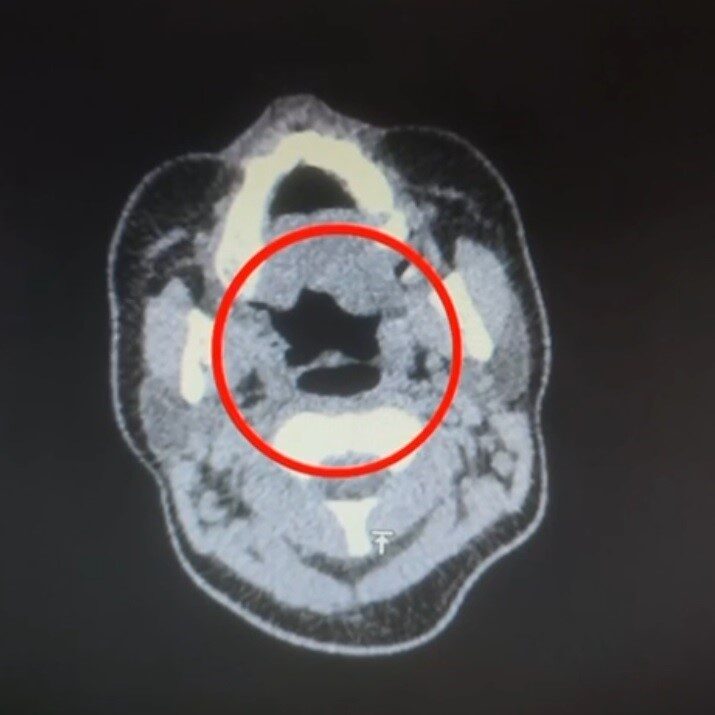

Hastanede yapılan iç beden muayenesinde, şüphelinin midesinde toplam 50 adet kapsül şeklinde uyuşturucu madde tespit edildi. Ele geçirilen bu maddelerin toplam ağırlığının 500 gram olduğu öğrenildi.